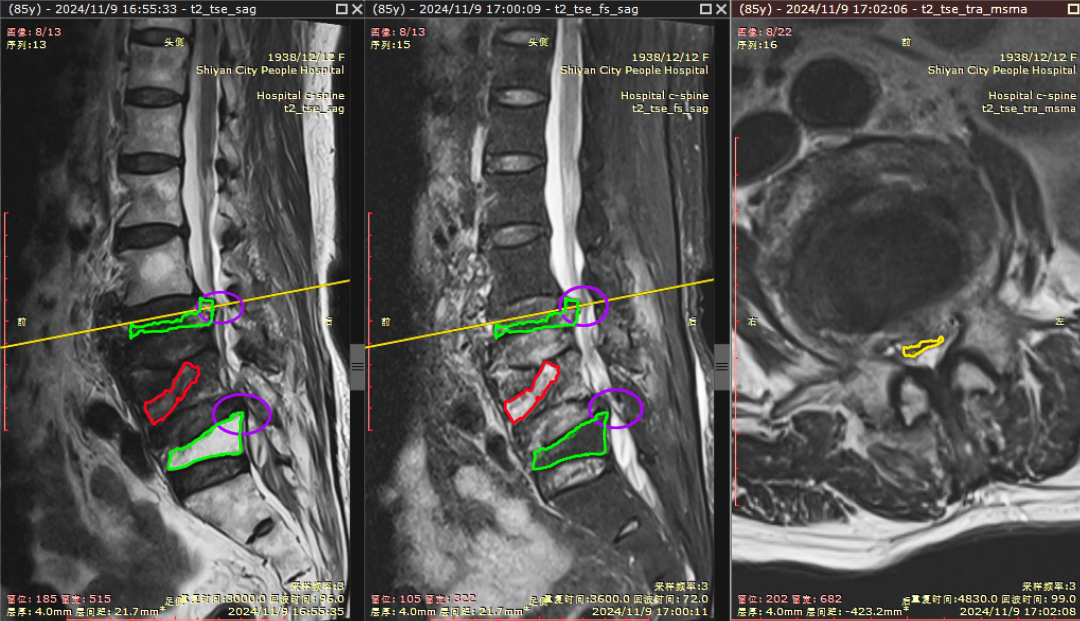

端水闪着腰,一查竟腰椎骨折!十堰人医:这类人群要警惕

今日房县网讯 “我就端了盆水,也没有跌倒,怎么就骨折了呢?”85岁的张奶奶百思不得其解。随着年龄的增大,大部分老年人都患有骨质疏松情况,严重时甚至打个喷嚏、咳嗽一声都有可能造成骨折。85岁张奶奶端盆水闪着腰疼痛难忍无法行走…